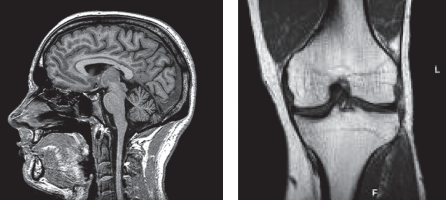

Magnetic Resonance Imaging is a type of scan that uses strong magnetic fields and radio waves to produce diagnostic images of the internal organs and structures of the body. An example of an MRI scanner is seen below. The patient lies inside the scanner during the examination and is given ear protection to minimise the effects of the noise which the scanner makes. Headphones are available through which music may be played. You may bring along your own CD/Mp3 player if you wish.

MRI produces high quality images of most parts of the body. These include:

- Brain and spinal cord

- Muscles, bones and joints